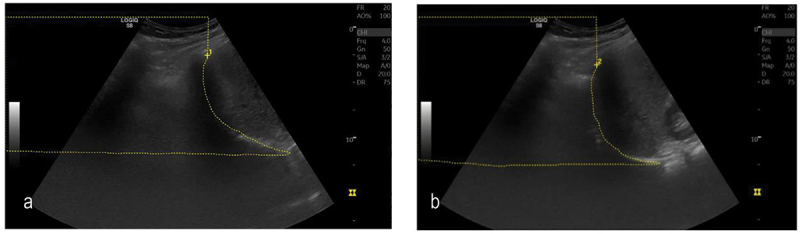

Methods: In a prospective, observational study, patients with recurrent unilateral pleural effusion underwent US evaluation of effusion characteristics and diaphragm movement measured by M-mode and the Area method before and right after drainage. The level of dyspnoea was assessed using the modified Borg scale (MBS). A minimal important improvement in dyspnoea was defined as delta MBS ≥ 1.

Abstract Image